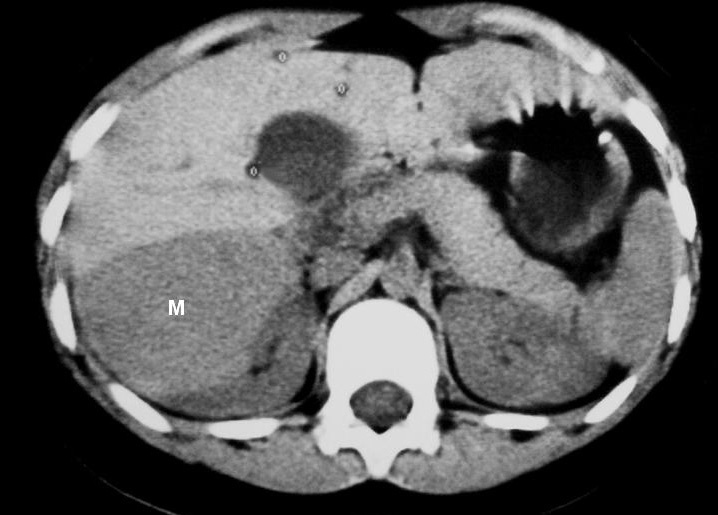

La única paciente con angiomiolipoma renal fue una niña de 10 años con esclerosis tuberosa. En el riñón derecho se identificó una tumoración en el polo superior, con gran crecimiento extrarrenal, densidad homogénea, mayor que la del parénquima renal y menor que la del hígado y relativamente ecogénica (fig. 9). No se constataron áreas grasas, tratándose de un angiomiolipoma con poco componente graso. En el riñón izquierdo se identificaron dos lesiones de pequeño tamaño con atenuación grasa compatibles con angiomiolipomas. Como hallazgos asociados se observaron en el hígado múltiples lesiones con contenido graso de características similares, compatibles con angiomiolipomas intrahepáticos.

Fig. 9. Angiomiolipoma. Niña con esclerosis tuberosa. (A) Ecografía abdominal. Corte renal derecho. Masa renal de ecogenicidad heterogénea y contornos lobulados. (B) Tomografía computarizada abdominal. Masa (M) en riñón derecho. No se identifica componente graso. En el hígado existen tres lesiones de atenuación grasa correspondientes a angiomiolipomas hepáticos (1, 2, 3).